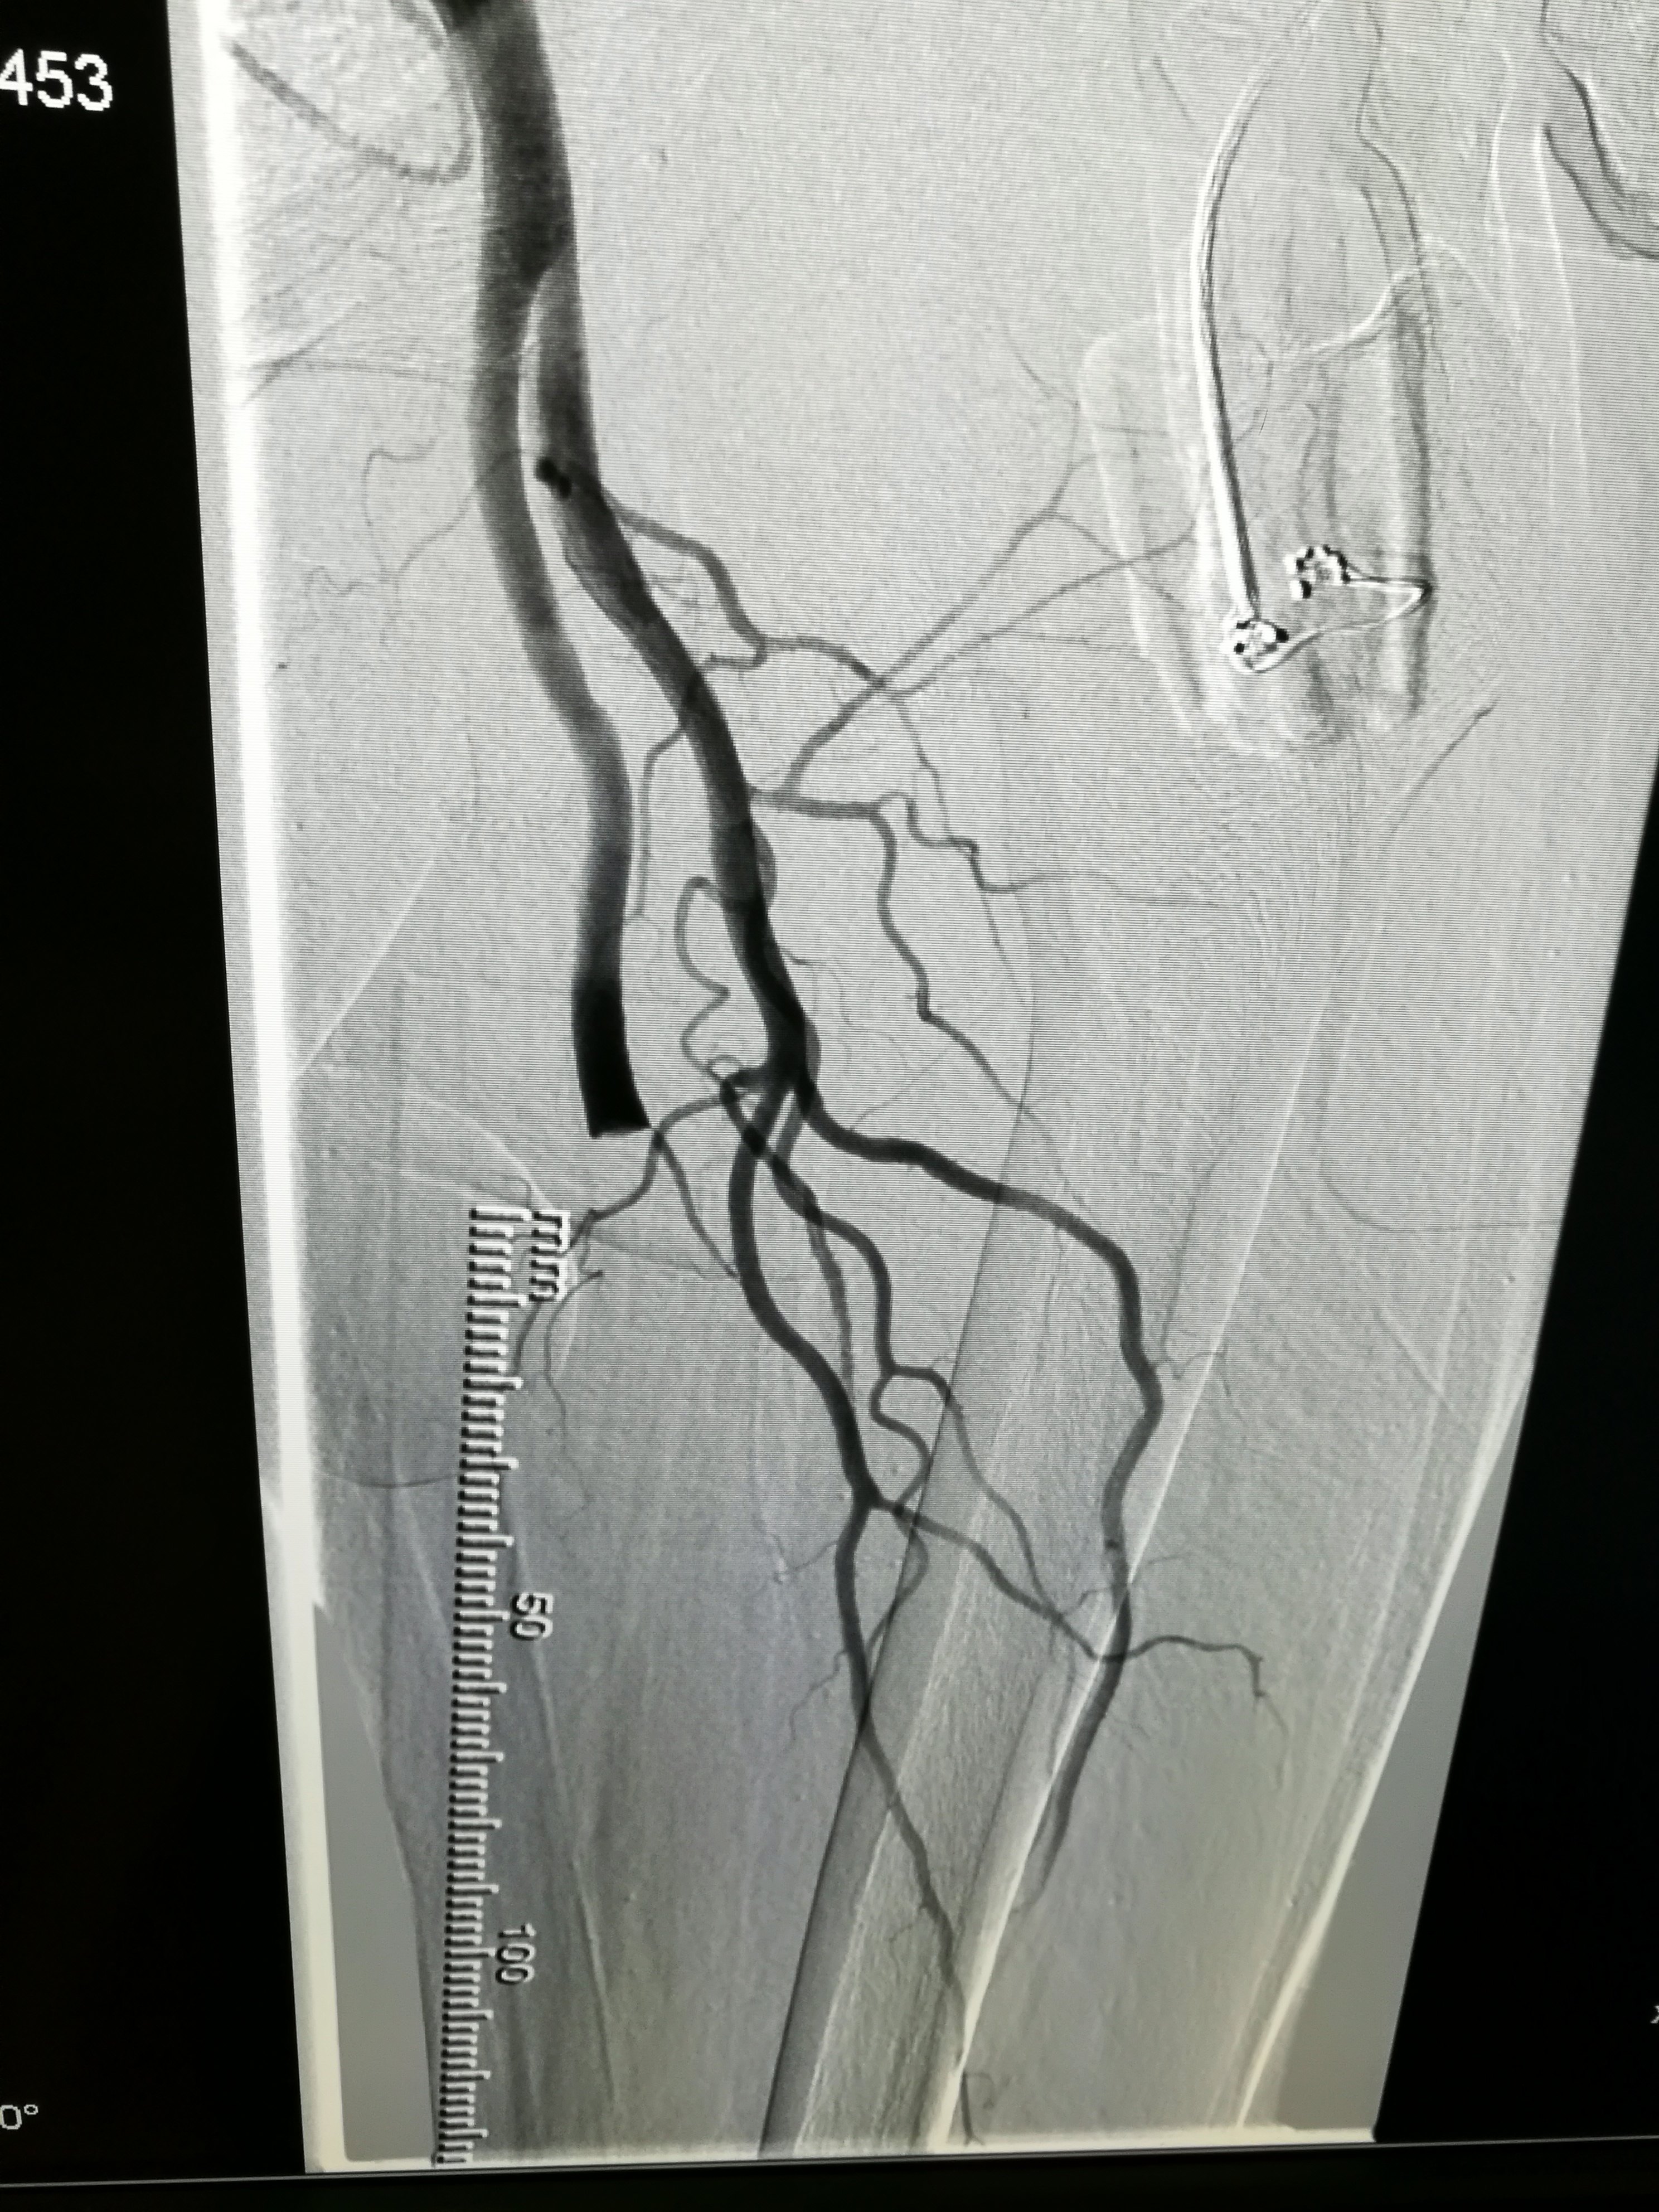

急性下肢动脉栓塞手术前后表现1

取出的血栓取栓后即刻的下肢动脉造影造影显示血管通畅这只是治疗的一